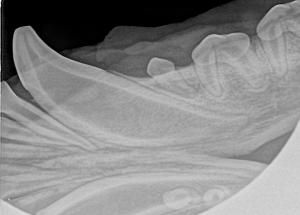

Feline Full Mouth Radiograph example